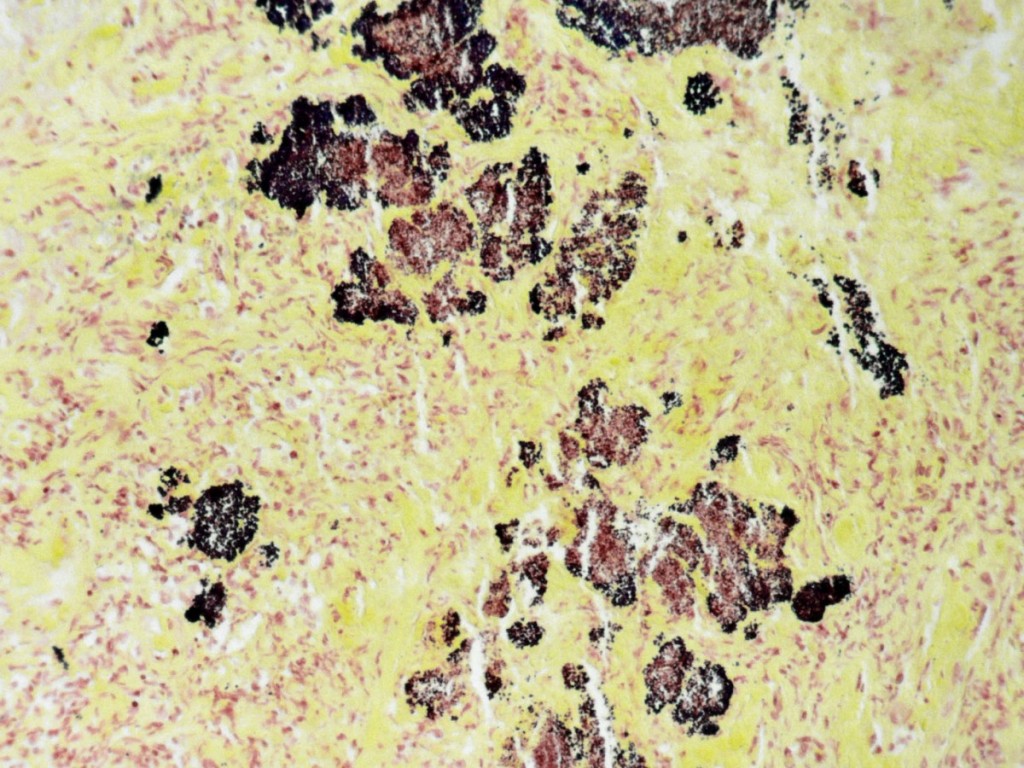

![Botryomycosis (click on photo to enlarge) [source: www.huidziekten.nl] Botryomycosis](../../../images/botryomycosis-2z.jpg) |

| botryomycosis |

botryomycosis |